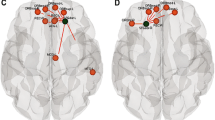

Group differences among sensorimotor network metrics as well as relationships with function are portrayed in Fig. 3. Betweenness centrality of TDC M1 (309 ± 120) was higher (H(2,82) = 52.63; p < 0.001) than AIS (68 ± 65; p < 0.001), and PVI (62 ± 55; p = 0.003). Clustering coefficient of TDC M1 (138 ± 23) was lower (H(2,82) = 59.59; p < 0.001) than AIS (266 ± 75; p < 0.001) and PVI (226 ± 33, p < 0.001). Neighbourhood complexity of TDC M1 (0.018 ± 0.009) was lower (H(2,82) = 7.92; p = 0.019) than AIS (0.053 ± 0.050; p = 0.028) and PVI (0.058 ± 0.050; p = 0.020).

Sensorimotor network node analysis. Sensorimotor node differences between the dominant hemisphere of controls to the non-lesioned, intact hemisphere of both stroke groups are shown. For the simplicity of the diagram, both arterial and venous strokes were combined as they displayed no differences from each other in any of the nodes. Red circles represent the nodes where both stroke groups showed higher values compared to controls, yellow representing no difference, and blue representing nodes of lower values compared to controls. Vertical lines represent an inverse relationship between the respective graph theory metric at the node of interest and the AHA. Horizontal lines represent the same inverse relationship with the node, but in relationship to MA instead. S1 primary sensory cortex, M1 primary motor cortex, SMA supplementary motor area, IOG inferior occipital gyrus, AHA assisting hand assessment, MA Melbourne assessment.

Primary somatosensory cortex (S1)

Consistent with M1, betweenness centrality of TDC S1 (295 ± 137) was significantly higher (H(2,82) = 31.01; p < 0.001) compared to AIS (137 ± 110; p < 0.001) and PVI (112 ± 87; p < 0.001). Clustering coefficient was lower (H(2,82) = 44.26; p < 0.001) in TDC S1 (121 ± 24) compared to both AIS (211 ± 58; p < 0.001) and PVI (179 ± 36; p < 0.001). Neighbourhood complexity showed no differences (p = 0.13).

Supplementary motor area (SMA)

Betweenness centrality of TDC SMA (18.1 ± 17.2) was lower (H(2,82) = 26.28; p < 0.001) than AIS (87.8 ± 65.5; p < 0.001) and PVI (72.1 ± 66.7; p < 0.001). No other significant differences were found (all p > 0.19).

Subcortical gray motor areas (thalamus, caudate, putamen, pallidum)

Clustering coefficient of TDC thalamus (268 ± 78) was higher (H(2,82) = 19.3; p < 0.001) than both AIS (79 ± 26; p = 0.009) and PVI (58 ± 18; p < 0.001). No other graph theory metrics showed group differences for the other subcortical areas (all p > 0.24).

Inferior occipital gyrus (IOG)

No differences were observed between any of the groups for any metrics in the IOG (p = 0.42).

Motor network metrics and clinical motor function